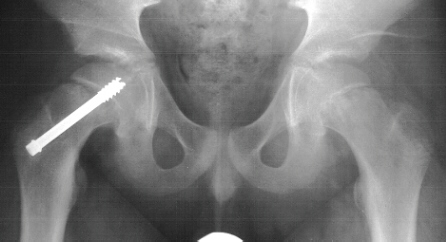

An AP pelvis and frog-leg lateral radiographs of both hips were obtained.

On the AP pelvis radiograph, there was notable widening and irregularity

of the proximal femoral epiphyseal growth plate, and Klein's line did not

intersect the epiphysis

The frog-leg lateral view of the right hip demonstrated an obvious grade

1 slipped capital femoral epiphysis

.

The patient was admitted to the hospital, placed on strict bedrest,

and he had an in situ pinning of his right hip the next day. There were

no postoperative complications, and he was discharged one day later. By

the time of his follow-up visit three weeks later, he was riding his bike

and had discarded his crutches. An AP pelvis

and frog-leg lateral radiographs of both hips were obtained which were